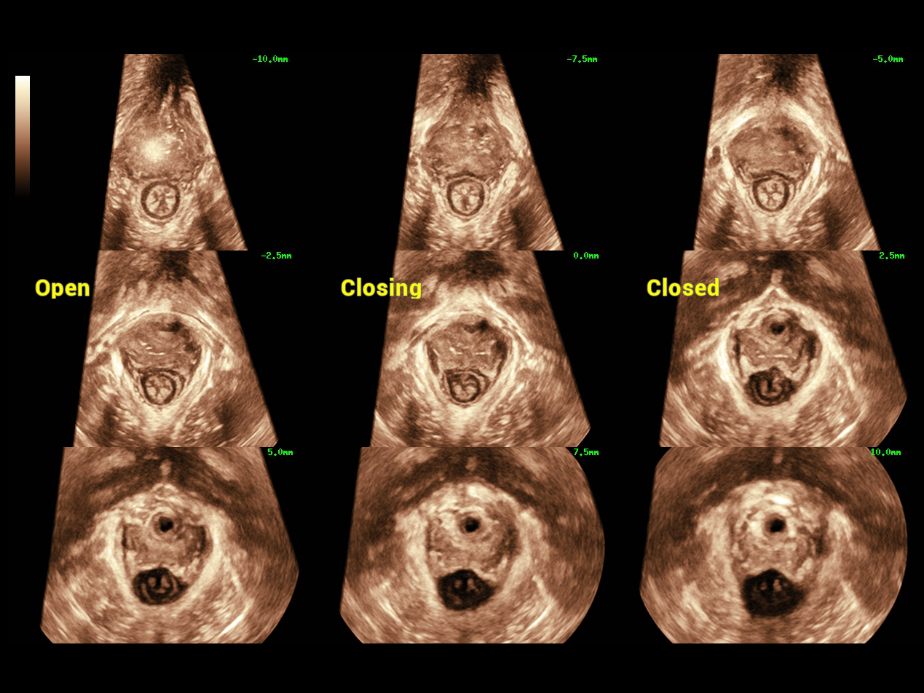

Die Verwendung von Ultraschall im Bereich der Urogyn?kologie findet unter ?rztinnen und ?rzten zunehmend Beachtung. Sie kann die Diagnose der weiblichen Beckenbodendysfunktion (FPFD) sowie pr?- und postoperative Evaluationen erleichtern.

Bei der FPFD-Prognose mittels Ultraschall verfolgen ?rztinnen und ?rzte einen globalen Ansatz, der die umfassende, akkurate Diagnose der vorderen, mittleren und hinteren Teile des Beckens vorsieht, mit einer gro?en Zahl daf├╝r n?tiger 2D-Messungen, 3D-/4D-Bildgebung und Evaluationen usw. Die Untersuchung ist zeitaufwendig und unangenehm, was hohe Anforderungen an die Bildgebungsmodi und die Messgeschwindigkeiten stellt.

Nuewa bietet automatische 2D-Vermessungen der Beckenabschnitte sowie ein intelligentes Volumenberechnungssystem, einschlie?lich automatisierter Berechnung des Hiatus Levatorius und der Analyse mehrerer Abschnitte.